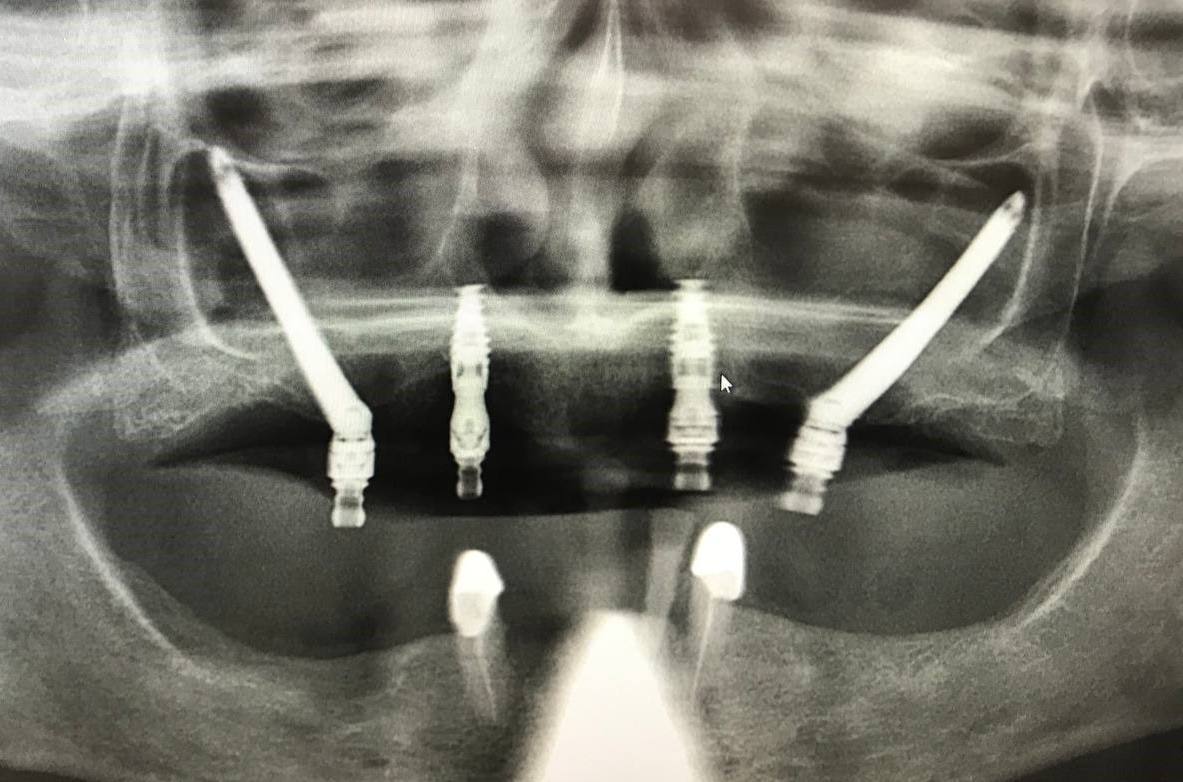

2024-06-06 в 11:00, admin, рубрики: здоровье, зубы, клиника, лечение, пациент, стоматологияСергей, технический директор ИТ-компании, пришёл к нам с весьма характерной историей и классической картиной «рта айтишника». У него были абсцесс, стёртые жевательные зубы, сильный запах изо рта и стоматофобия. Но больше, чем стоматологов, он боялся бросить лечение на середине пути, как уже бывало в прошлом.

А дальше он потерял сознание и 2,7 миллиона рублей. Но зато когда очнулся — перестал резать язык о зубы и стесняться разговаривать с людьми.

Изначальный запрос выглядел так: «Нет сил это терпеть, снесите мне все зубы и сделайте вставную челюсть». Сразу скажем, что получил он совсем не это.

Ниже будет история о том, как это лечение выглядело со стороны: рассказывает сам Сергей и я, его курирующий врач-ортопед Артём Абакумов.Читать полностью »